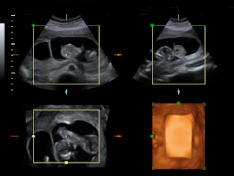

Vemos tres planos de un embarazo de trillizos en ecografía 2D en diferentes cortes de imagen. Lo que vemos en 3D es lo que los ecografistas conocen como "un queso", es decir el embarazo visto en tres dimensiones desde una perspectiva determinada. Lo que realmente esconde ese peculiar queso...